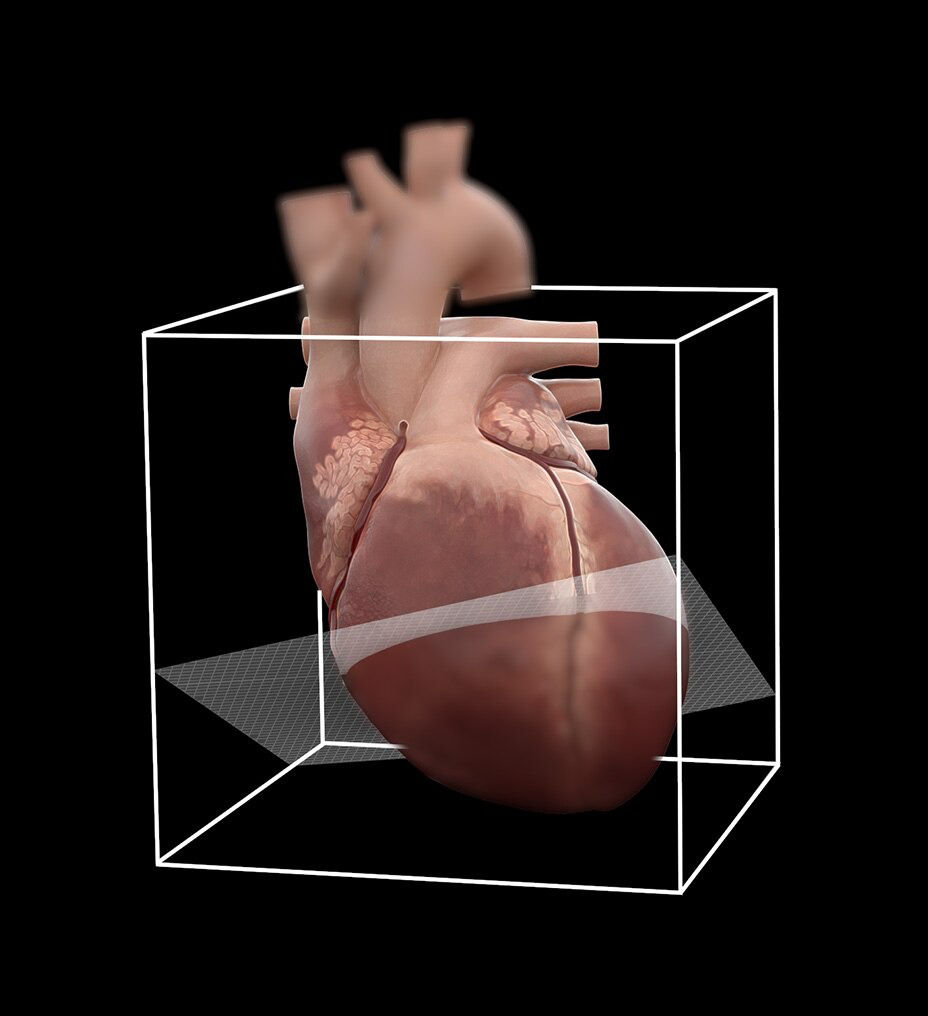

The ECG-less CT (a cardiac CT scan without an ECG trace) is an industry-first

Increases Cardiac CT access

Address cardiac exams where patient access and speed need to be prioritized